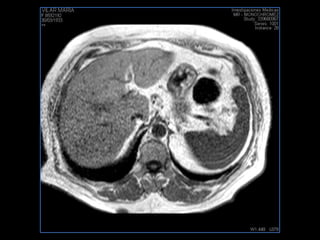

PROTOCOLO hígado graso AXIAL in phase y out phase AX T1 y AX fat sat +SAG T2  CON   GADOLINIO :  COR T1+AX T1(DIN) SAT: NO  FASE: RL THK: 4MM  COIL:  GAP: (FACTOR 1.4)  FOV: 40 CM NEX:2 SINCRONIZACION RESPIRATORIA EN 3 O 4 CICLOS ALE

PROTOCOLO hemocromatosis AXIAL supresión grasa /AX multieco en higado COR T2 AX T1 +SAG T2  CON   GADOLINIO :  COR T1+AX T1 SAT: NO  FASE: RL THK: 4MM  COIL:  GAP: (FACTOR 1.4) 1MM FOV: 40 CM NEX:2 SINCRONIZACION RESPIRATORIA EN 3 O 4 CICLOS ALE

PROTOCOLO pancreas/ riñon AXIAL fat sat /AX in phase out phase AX T1 +SAG T2  COR T2, CON   GADOLINIO :  COR T1+AX T1(DIN) SAT: NO  FASE: RL THK: 4MM  COIL:  GAP: (FACTOR 1.4) 1MM FOV: 40 CM NEX:2 SINCRONIZACION RESPIRATORIA EN 3 O 4 CICLOS ALE